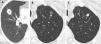

(A–F) Diffuse lung disease at baseline LDCT. Advanced destructive pulmonary emphysema (A–C) in a 65-year-old man from NLST who died of respiratory disease (ICD code J449) 835 days after randomization. Interstitial lung disease (D–F) in a 73-year-old man from NLST who died of respiratory disease (ICD code J849 – interstitial pulmonary disease unspecified) 2462 days after randomization.